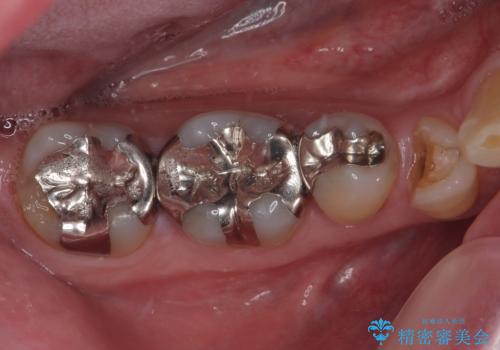

銀歯の下の虫歯を治したい オールセラミッククラウン・セラミックインレー修復